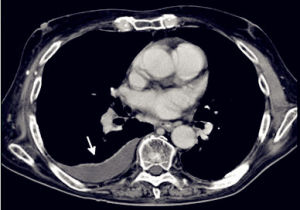

影像診斷胸腔積液量0.3~0.5L時,X線僅見肋膈角變鈍;更多的積液顯示有向外側、向上的弧形上緣的積液影。平臥時積液散開,使整個肺野透亮度降低。液氣胸時積液有液平面。大量積液時整個患側陰暗,縱隔推向健側。積液時常邊緣光滑飽滿,局限於葉間或肺與膈之間,超聲檢查有助診斷。治療